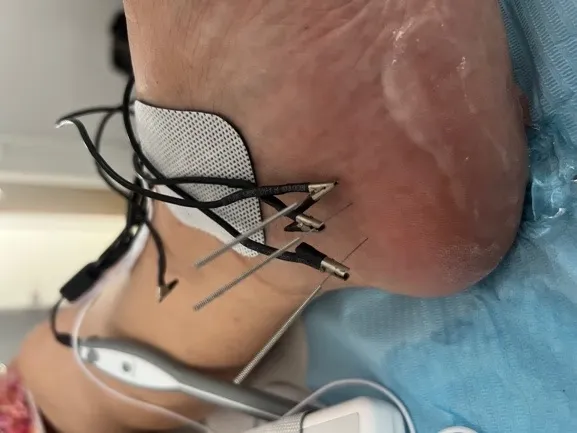

Diagnóstico preciso con ecografía

El primer paso es identificar exactamente qué está causando tu dolor. Con nuestros dos ecógrafos de última generación, podemos visualizar en tiempo real las estructuras del pie: nervios, tendones, tejidos blandos y posibles lesiones. Esto es especialmente útil para diagnosticar neuromas de Morton y valorar la profundidad de úlceras.

Terapias regenerativas avanzadas

Para patologías inflamatorias y lesiones crónicas, aplicamos tecnologías de última generación:

INDIBA (radiofrecuencia): terapia complementaria que aplicamos con el objetivo de favorecer el aporte sanguíneo a la zona y mejorar tu confort durante la rehabilitación. Su base de evidencia es limitada y nunca es el tratamiento principal. No la aplicamos sobre heridas ni úlceras abiertas.

Terapia láser de alta potencia: la valoramos como coadyuvante, con evidencia limitada. No prometemos un efecto ni un plazo.